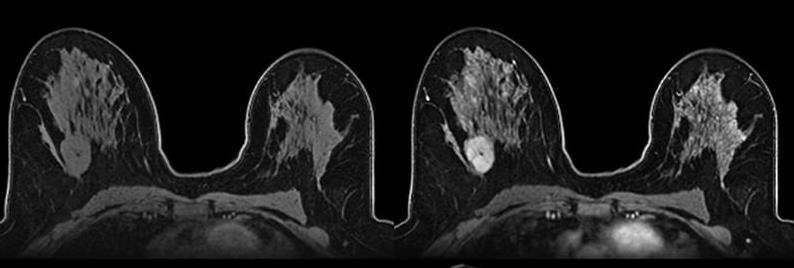

Daher ist Salataris AI angetreten, um mit Hilfe von Deep-Learning-Technologien bisherige Verfahren zu unterstützen und die Bildqualität zu verbessern. Deep Learning ist ein Bereich der künstlichen Intelligenz, bei dem sogenannte neuronale Netzwerke große Datenmengen analysieren und daraus selbstständig Muster und Zusammenhänge erkennen. Anders als herkömmliche Programme müssen sie nicht manuell programmiert werden, sondern lernen direkt aus den Bilddaten. Mit Unterstützung von EuroCC Austria trainierte das Team von Salataris AI auf dem italienischen Supercomputer Leonardo mehrere Modelle, sowohl für überwachtes als auch unüberwachtes Lernen und erreichte damit ihr Ziel: Bessere Bilder. Alle hier beschriebenen Methoden wurden vollständig umgesetzt (siehe Fotos weiter unten).

Beim Betrachten von Mammografien oder MRT-Bildern ist es manchmal schwierig, Tumoren von gesundem Gewebe zu unterscheiden. Es kann sein, dass ein Tumor und das umliegende Gewebe gleich hell sind, die Pixelintensität also kaum variiert. Genau hier setzen Kontrastverstärkungs-Netzwerke an. Sie sind eine besondere Art von Deep-Learning-Modellen, die das Bild analysieren und erkennen, welche Bereiche besonders wichtig für die Diagnose sein könnten – etwa verdächtige Strukturen oder Gewebsveränderungen. Anschließend verändern sie gezielt den Kontrast in genau diesen Bildbereichen. Tumorregionen werden dadurch heller oder schärfer dargestellt, während das umliegende normale Gewebe in seiner Darstellung abgeschwächt wird. So entstehen Bilder, auf denen mögliche Tumore deutlicher sichtbar sind.